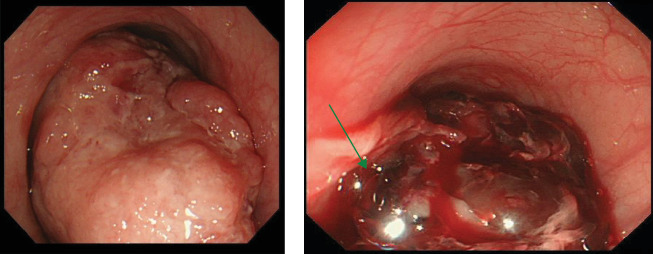

Esophageal bleeding management typically involves endoscopy but becomes challenging with large or hemorrhagic tumors, especially in cases of rare basal cell carcinoma. This malignancy, with a poorer prognosis than squamous cell carcinoma, often requires definitive surgery. A 78-year-old man with severe hematemesis underwent transarterial embolization (TAE) after failed endoscopic hemostasis for a middle thoracic esophageal tumor. Subsequently, he successfully underwent radical tumor resection on the seventh day of hospitalization. While emergency surgery is an option, its invasiveness may be a limitation, especially for patients in poor general condition. TAE is effective for hemostasis and serves as a crucial bridge to radical esophageal tumor resection.